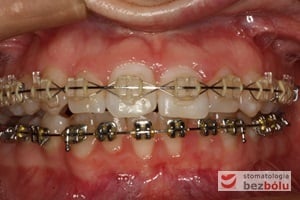

Leczenie bezekstrakcyjne z wykorzystaniem strippingu

Pacjentka lat 22 zgłosiła się do naszej placówki celem podjęcia leczenia ortodontycznego. Głównym oczekiwaniem pacjentki była poprawa estetyki uśmiechu oraz brak ekstrakcji zębów na drodze do jej uzyskania. Ze względu na liczne stłoczenia zębów w górnym i dolnym łuku, dość duży materiał zębowy w porównaniu z bazą kostną, a także zgryz przewieszony boczny prawostronny po dokładnej analizie cefalometrycznej oraz analizie modeli diagnostycznych zastosowano leczenie bezekstrakcyjne z wykorzystaniem strippingu jako alternatywy dla usuwania zębów, mającego na celu uzyskanie miejsca w łuku na uszeregowanie zębów. Po fazie aktywnego leczenia trwającego 18 miesięcy zastosowano leczenie retencyjne w postaci szyny retencyjnej w łuku górnym oraz retainera stałego w łuku zębowym dolnym klejonego od kła do kła.